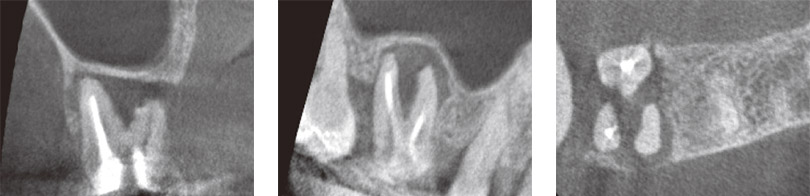

7の打診を主訴に来院された患者さんのレントゲン写真。

デンタルレントゲン写真やパノラマレントゲン写真で見分けのつきにくい7、根尖にぼんやりと透過像が見えるが…。 -

骨の厚みによってぼんやりとしか見えなかった透過像もCTでは明瞭になり、頰側に裂開しており、かつ樋状根であることもわかる。